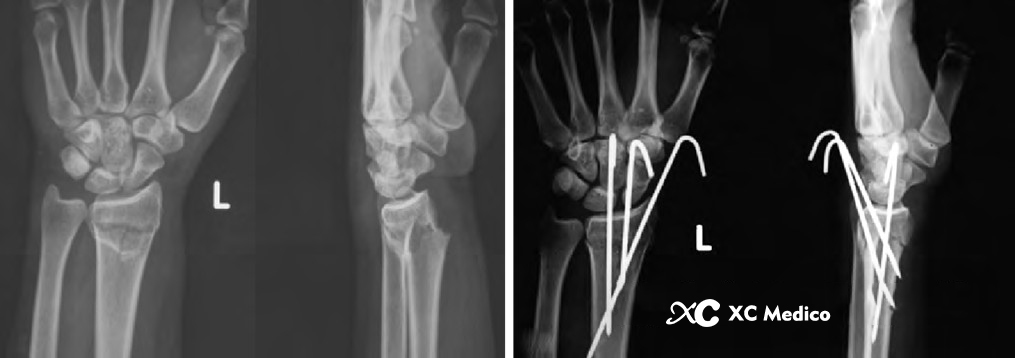

Во -первых, выполняется закрытое восстановление перелома, с медленной и непрерывной тягой, а дорсальное и радиальное смещение корректируется с помощью сгибания пальма и локтевого отклонения. После сокращения рука помещается на свернутый лист, поддерживая пальмовое сгибание и локтевое отклонение (рис. 2а, б) и фиксируется не менее трех чрескожных проводов Киршнера.

Третий K-провода фиксируется к фрагменту Lunate Fossa Bone 0,5 см дистально до линии сустава запястья, расположенной между четвертым и пятым компартментами разгибателей. K-провода прикреплена к ладонильной стороне радиуса под углом 45 °, как показано на рисунках A и B ниже.

Классическая чрескожная фиксация проволоки Киршнера расстановки дистального радиуса показана на рисунках AE ниже.